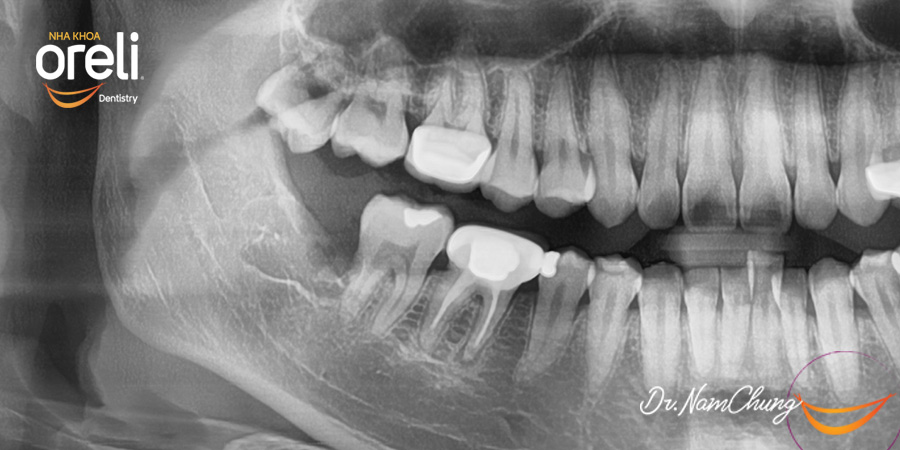

Ca nhổ răng khôn ảnh hưởng răng bên cạnh – Điều trị tại Oreli

Nhổ răng khôn

Mọc lệch